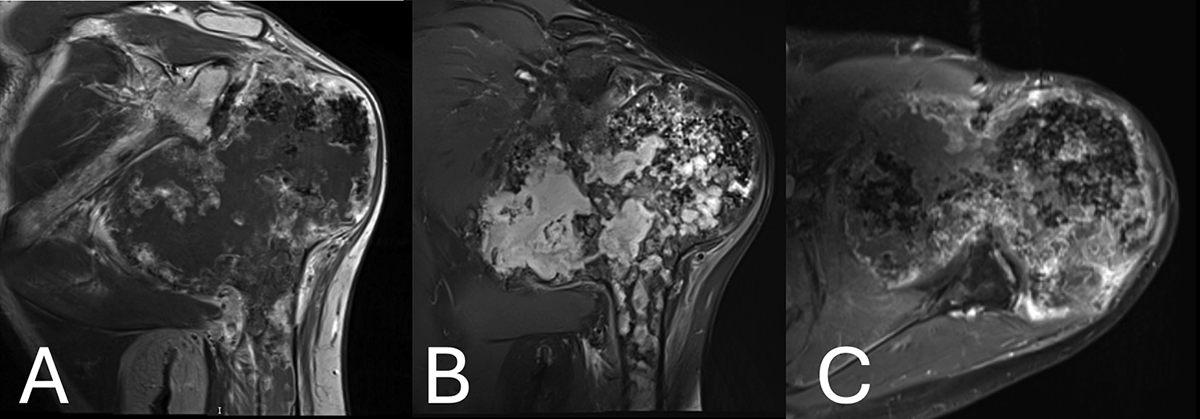

Figure 3

(A) Magnetic resonance imaging showing the exuberant medial compartment, denoted as a large lobulated area, extending to the cortex, with low signal intensity on T1W. (B) Magnetic resonance imaging showing High signal intensity on fat-suppressed T2 W images of the lobulated area on the MRI. Flocculent stippled areas of a signal void, representing cartilaginous calcifications, were more prominent in the lateral compartment. Geographic areas of marrow signal, which are high on T1W and low on fat-suppressed T2W, were entrapped within the cartilaginous tissue of the medial compartment, whereas bone marrow signal was seen at the periphery of the lateral compartment. Cortical disruption was seen at the posterior aspect of the epiphysis corresponding to the osteolytic areas shown on CT. (C) Magnetic resonance imaging post gadolinium administration showing mild peripheral inhomogeneous enhancement. Tissue enhancement was more diffuse or nodular and somewhat more intense at the posterior aspect adjacent to the osteolytic area. Lobules of cartilaginous signal intensity were also seen in the middle and lateral components of the epiphysis, extending to the metaphysis.